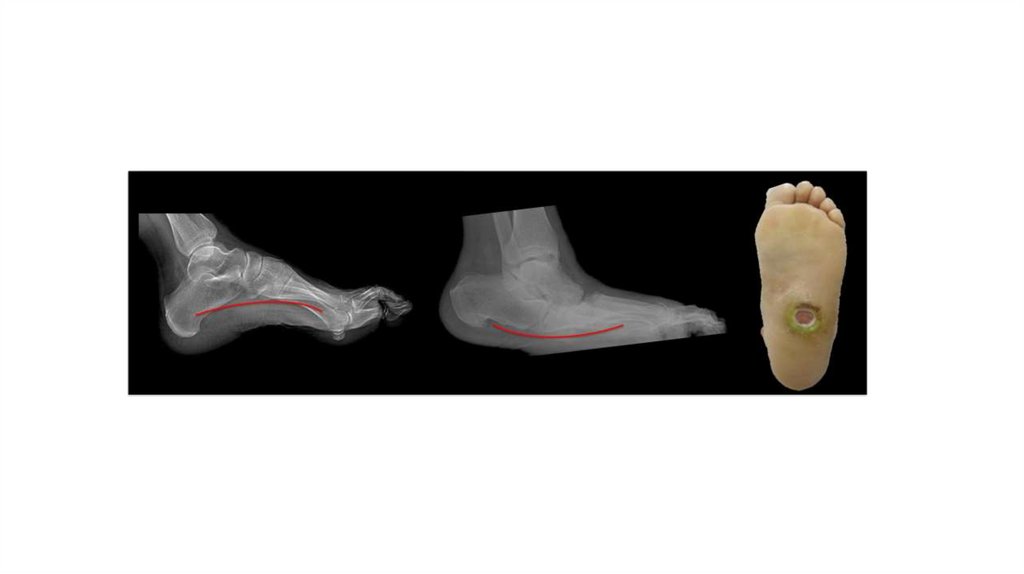

Развитие нейропатических язв

СДС нейропатическая форма Признаки нейропатической язвы

Диабетическая нейроостеоартропатия (ДНОАП, артропатия Шарко) -

Стадии развития диабетической остеоартропатии

Стадии ДОАП 1 стадия – острая 2 стадия - подострая

Стадии ДОАП